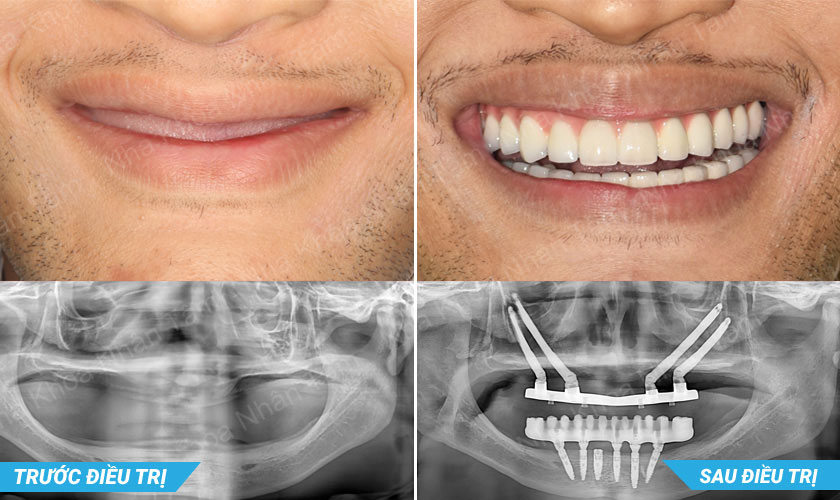

Ts.Bs Võ Văn Nhân thực hiện cấy ghép Implant xương gò má thành công

Quá trình cấy ghép Implant xương gò má của TS.BS Võ Văn Nhân sẽ được thực hiện tại bệnh viện với sự hỗ trợ của ê kíp chuyên nghiệp, cùng với đó là hệ thống máy móc, trang thiết bị hiện đại, đảm bảo yếu tố vô trùng - vô khuẩn.

TS.BS Võ Văn Nhân đã thực hiện thành công ca phẫu thuật cấy 2 Implant xương gò má (*) ở vùng răng sau và phục hồi răng tức thì cho khách hàng có xương hàm trên bị tiêu trầm trọng.

Implant xương gò má là giải pháp tối ưu cho bệnh nhân có xương hàm trên bị tiêu trầm trọng

Ts.Bs Võ Văn Nhân đã thực hiện thành công rất nhiều ca implant, đem lại cơ hội và hy vọng cho khách hàng, giúp họ phục hồi chức năng ăn nhai và thẩm mỹ, cải thiện chất lượng cuộc sống và tự tin hơn trong giao tiếp.

Thành công của tiến sĩ, bác sĩ Võ Văn Nhân được đánh giá là bước tiến mới trong lĩnh vực implant nha khoa Việt Nam, góp phần nâng cao hiệu quả điều trị phục hồi chức năng ăn nhai và thẩm mỹ cho những trường hợp có tình trạng lâm sàng phức tạp và bất lợi. Đây là những trường hợp mà kỹ thuật trồng răng cổ điển không giải quyết được.